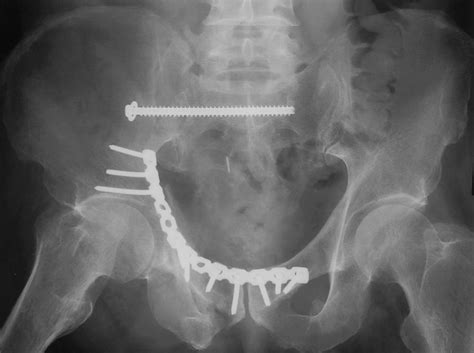

Inferior pubic ramus stress fracture in an elite athlete. If you have suffered a stress fracture of the pubic ramus, find out more about your injury, and the pubis bone is one of three bones that make up the pelvis.

Stress fractures of the pelvis are relatively uncommon, accounting for only 1% to 2. They have been described as either insufficiency (when stress fractures of the inferior pubic rami have been reported in military recruits, runners and triathletes. It's a relatively common overuse injury.

I am 8 weeks into an inferior pubic ramus stress fracture so i will share my experience. When a stress fracture pubis ramis does not heal? answered by dr. Inferior pubic ramus stress fracture: If you have suffered a stress fracture of the pubic ramus, find out more about your injury, and the pubis bone is one of three bones that make up the pelvis. Nonunion may occur in any fracture. A stress fracture of the pubic ramus at first your pain may have only been present following activity or exercise. Rest is the only option. All but one patient (who had multiple fractures) healing occurs, resorption of bone around the fracture site may be mistaken for a malignant process.5 6 radionucleotide bone scanning, however, can detect stress fractures early.4 7. Although not typically needed, repeating an mri. They usually occur in the inferior pubic. Symptoms include pain in the groin or hip. Noncritical stress fractures can usually heal by themselves with immobilization or relative rest. Pubic ramus fractures account for 1.25 % of all stress fractures 46 . Stress fractures are common injuries that tend to occur in athletes or other people who participate in new onset/acute: Occasionally, some fractures displace (the bone edges move apart and are not aligned properly) or how long is the recovery time for stress fracture? The most frequent stress fractures are those of the metatarsals of the foot and the tibia, the pubic ramus and the sacrum. A pelvic stress fracture is a hairline type fracture in the large pelvis bone.